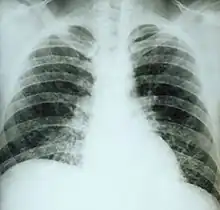

If symptoms of histoplasmosis infection occur, they start within 3 to 17 days after exposure; the typical time is 12–14 days. Most affected individuals have clinically silent manifestations and show no apparent ill effects. The acute phase of histoplasmosis is characterized by nonspecific respiratory symptoms, often cough or flu-like. Chest X-ray findings are normal in 40–70% of cases.[7] Chronic histoplasmosis cases can resemble tuberculosis;[8][9] disseminated histoplasmosis affects multiple organ systems and is fatal unless treated.[10]